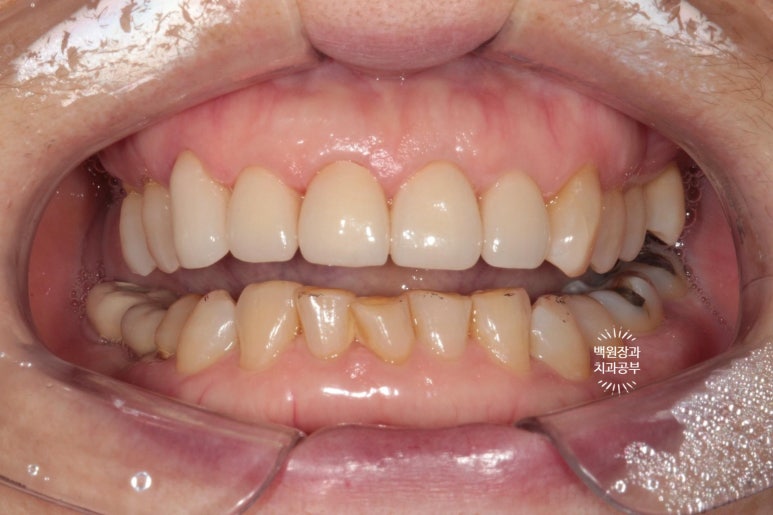

처음 내원하셨을 때 정면 사진입니다.

딱 봐도 위 대문니 두개에 큼지막한 세로 금이 관찰되네요. 환자분의 걱정 포인트이자, 콤플렉스였던 앞니 금.

생긴지 오래 되었을터인데, 시간이 흘러 착색까지 생겨버렸습니다. 50년 이상 사용한 치아에는 크랙이 많이 생길 수 있죠.

옆에서 보아도 너~무 잘 보이는 앞니 세로 금. 치아의 끝단에는 충치로 생각되는 어둑함이 자리잡고 있었고..

사진을 보시면 아시겠지만, 오른쪽 위 어금니 두개가 없으신 상태였습니다.

빼뚤빼뚤하기도 하면서, 금도 갖고 있었던 위 앞니들은 뒤에서 보면 이렇게 어둑하니.. 충치까지도 잘 보였습니다.